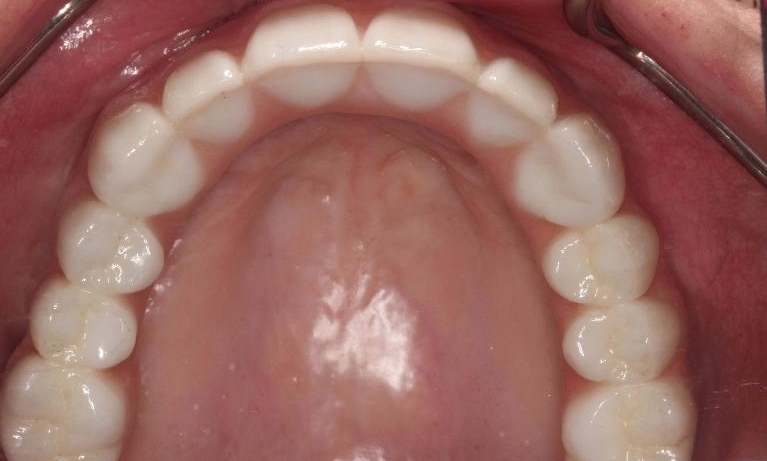

This patient came in without teeth! Had all of her teeth removed at a young age and couldn't wear a denture. We placed implants to support her new permanent teeth.